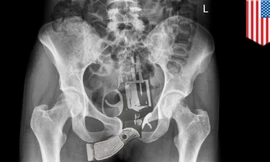

Phát hiện đối tượng giấu súng dạng bút trong hành lý tại sân bay Cát Bi

TPO - Phát hiện hành khách có biểu hiện nghi vấn khi đang làm thủ tục lên chuyến bay, lực lượng chức năng đã tiến hành kiểm tra và phát hiện một khẩu súng dạng bút trong hành lý.